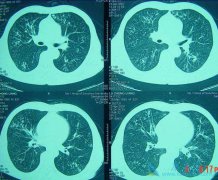

• 转移肺转癌是指的什么意思?移性肺癌症状有哪些症状?

转移肺转癌是指的什么意思?移性肺癌症状有哪些症状?

转移性肺癌的意思就是在患者体内的任何位置的恶性肿瘤都是通过各种方式转移到患者的肺部。大约有60%的恶性肿瘤在初次检查时就有肿瘤转移,其中30%~50%肿瘤转移到肺部。像不同的肿瘤转移到肺部的发生率不同,其中,甲状腺癌、乳腺癌、肾癌、绒毛膜癌、骨 ...